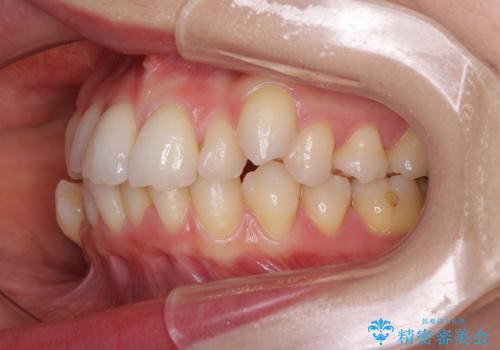

- 八重歯や前歯のデコボコを気にして来院された患者様です。

骨格的な左右差と、歯列から外れている歯が上下で左右非対称になっていることから、上下正中が歯1本分ずれている状態でした。

八重歯の改善と、上下の正中位置を極力合わせていくことを目的として、上下左右の第一小臼歯4本を抜歯し、ワイヤー装置にて矯正治療を行うこととしました。